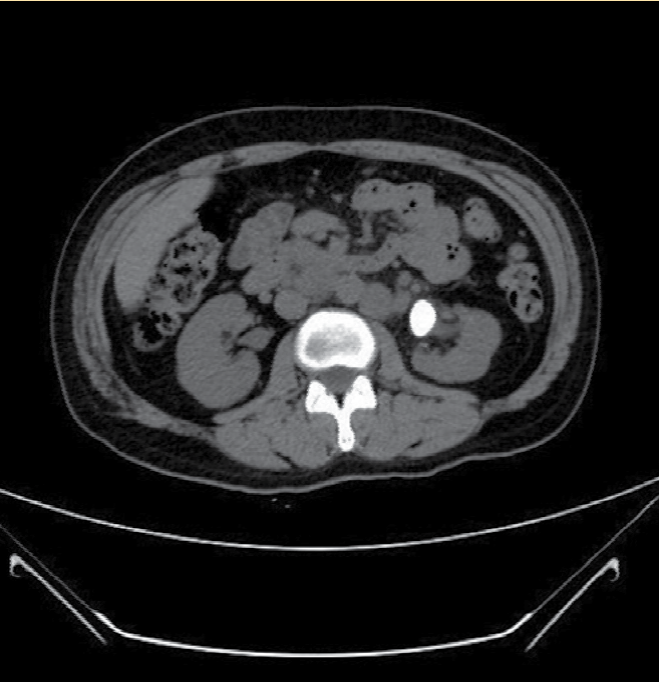

Se solicitaron exámenes paraclínicos de laboratorio completos que demostraron la presencia de leucocitosis a expensas de neutrofilia, con eritrocitos incontables por campo y cristales de oxalato de calcio regulares en el examen general de orina, con calcio sérico y niveles de paratohormona dentro de rangos normales. Se realizó una radiografía simple de abdomen que demostró la presencia de una imagen radiopaca. Dados los hallazgos se efectuó una urotomografía (UROTAC), y se apreció en el topograma una imagen redondeada radiopaca a nivel paravertebral izquierdo de L1 a L2 (Figura 1). En los cortes axial, coronal y en la reconstrucción tridimensional en fase simple y contrastada se hizo evidente una imagen hiperdensa en la pelvis renal izquierda con dimensiones de 2.19 × 1.54 × 2.58 cm e índice de atenuación de hasta 1762 unidades Hounsfield (Figura 2 3, 4), y se hizo el diagnóstico de litiasis piélica izquierda. Se inició impregnación antibiótica empírica previa toma de urocultivo y posteriormente se indicó tratamiento quirúrgico por medio de pielolitotomía laparoscópica izquierda. La evolución fue adecuada en el periodo postoperatorio. La paciente egresó al tercer día del postquirúrgico. Actualmente se encuentra en manejo multidisciplinario por endocrinología y urología, en espera del perfil metabólico para su adecuada categorización y tratamiento postevento lítico.

Figura 1 Topograma de urotomografía (UROTAC) con imagen paravertebral izquierda radiopaca a nivel L1-L2.